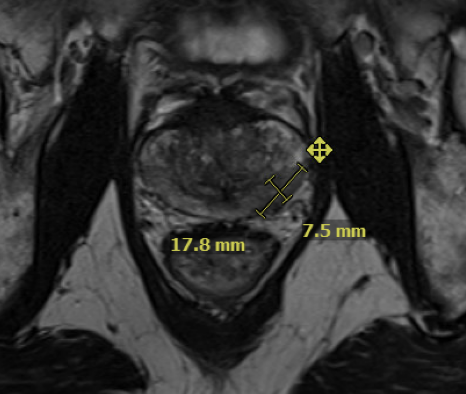

A prostate MRI revealed a 23-cc gland prostate (PSA density = 0.36), a PIRADS 5 abnormality in the left posterolateral base peripheral zone (Figure 1).